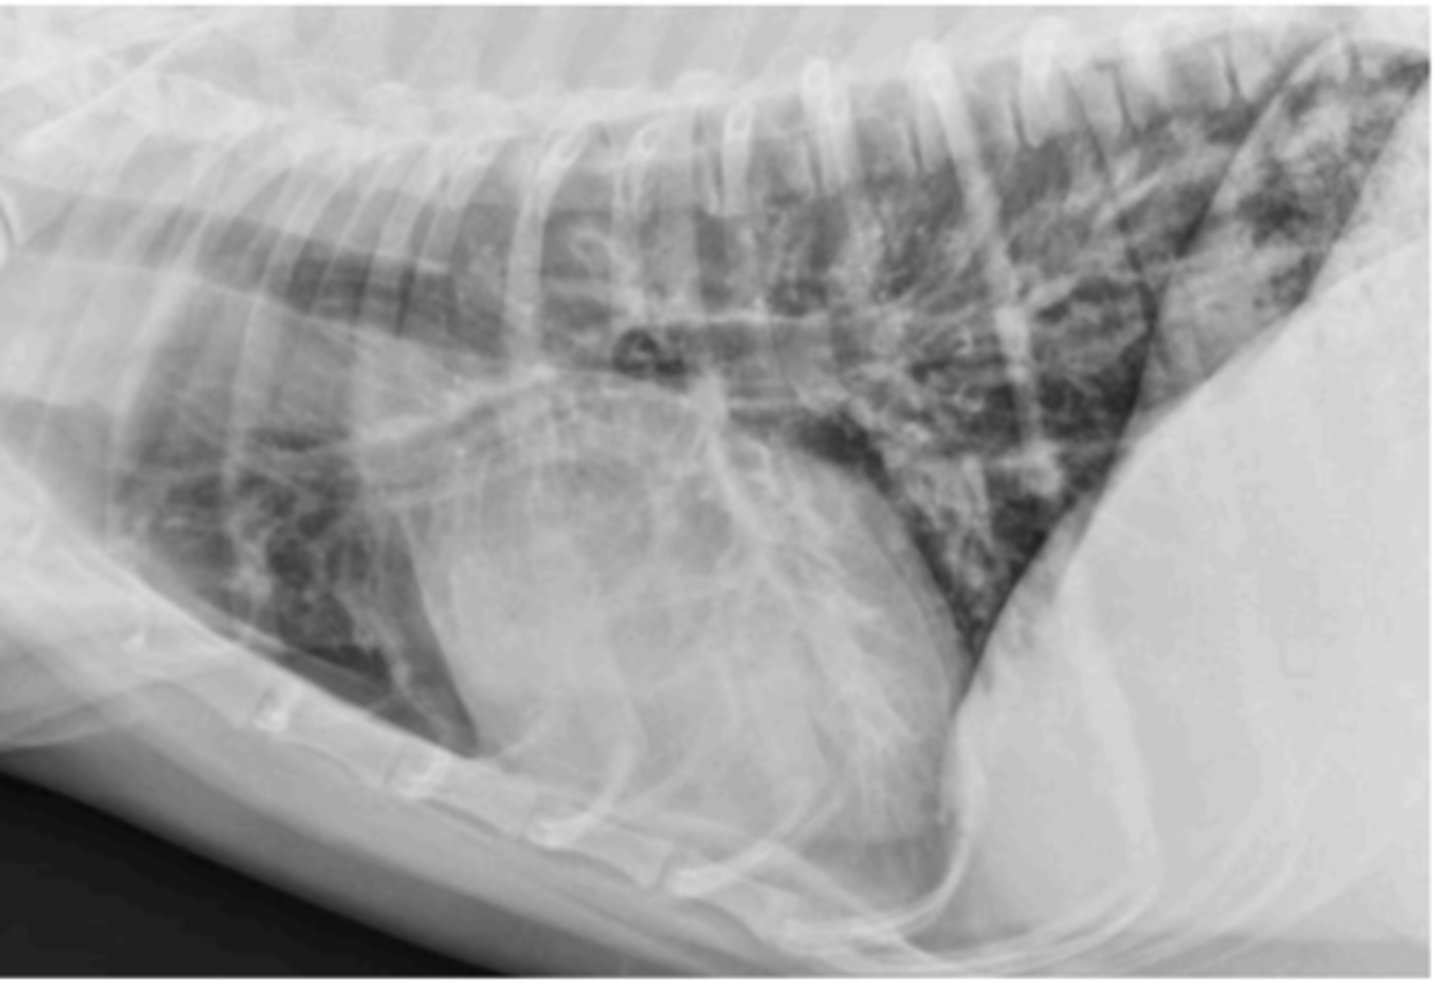

bronchial

What lung pattern is this?